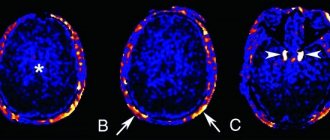

- Магнитно-резонансная томография – наиболее точный метод диагностики различных типов заболевания. Благодаря результатам МРТ можно определить наличие очагов демиелинизации, объем, расположение и причину возникновения глиального изменения.

Как выглядит глиоз головного мозга